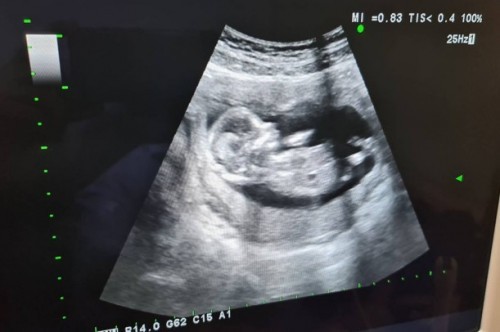

ผู้ชายคะ ซาวด์ตอน17+5วีคคะ